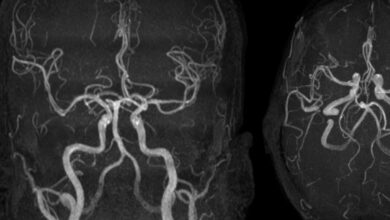

تلف الدماغ السام ينتج من التدخين مصر:إيهاب محمد زايد يرتبط تدخين الفنتانيل بتلف الدماغ السام في أول حالة تم الإبلاغ…